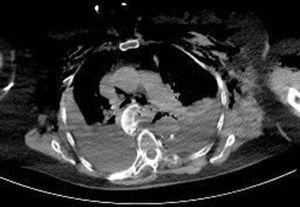

Mujer de 84años que, tras caída accidental por las escaleras, presentó politraumatismo. La tomografía axial computarizada (TAC) de tórax reveló la presencia de enfisema subcutáneo, hemoneumotórax, neumomediastino y fractura-luxación de la cabeza humeral izquierda con migración de la misma hasta el mediastino posterior a través de las fracturas presentes en los arcos costales izquierdos (figs. 1 y 2). Dada la ausencia de complicaciones cardiovasculares relacionadas con la presencia de la cabeza humeral en la cavidad pleural, se desestimó el tratamiento quirúrgico para su extracción. La paciente fue tratada de forma conservadora mediante la colocación de tubos de drenaje torácico bilaterales.